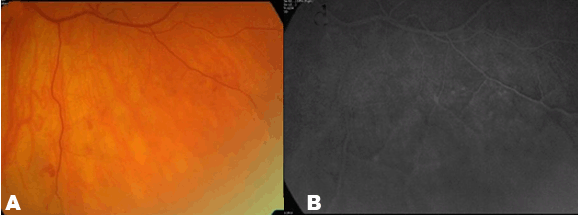

Case 2: A 60 year old female patient was referred because of bleeding in the lower mid-peripheral retina of the left eye noticed by an optician during routine visit. She had had no ocular problems but was on treatment for hypertension. Her vision with correction was normal at 20/25 in the right eye and 20/20 in the left eye. Dilated fundoscopy, revealed bilateral retinoschisis located inferior-temporally in the right eye and inferiorly in the left. There was evidence of neovascularization in the inner layer of the retinoschisis associated with small vitreous hemorrhage in the left eye. (Figure 2A) The fluorescein angiography showed hypoperfusion in the area of the retinoschisis in the left eye and hyperflourescence in the location of the neovessels. (Figure 2B) In order to prevent further vitreous hemorrhage, the patient underwent barrier argon laser photocoagulation. The patient has remained symptom free with no further vitreous hemorrhage in the last 18 months after the laser treatment. | ||||||